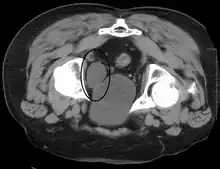

Cancer

Cross-section of the bladder showing a cancer within it. When a cancer occurs it is most likely to be a transitional cell carcinoma.

Cancer of the bladder is known as bladder cancer. It is usually due to cancer of the urothelium, the cells that line the surface of the bladder. Bladder cancer is more common after the age of 40, and more common in men than women;[29] other risk factors include smoking and exposure to dyes such as aromatic amines and aldehydes.[29] When cancer is present, the most common symptom in an affected person is blood in the urine; a physical medical examination may be otherwise normal, except in late disease.[29] Bladder cancer is most often due to cancer of the cells lining the ureter, called transitional cell carcinoma, although it can more rarely occur as a squamous cell carcinoma if the type of cells lining the urethra have changed due to chronic inflammation, such as due to stones or schistosomiasis.[29]

Investigations performed usually include collecting a sample of urine for an inspection for malignant cells under a microscope, called cytology, as well as medical imaging by a CT urogram or ultrasound.[29] If a concerning lesion is seen, a flexible camera may be inserted into the bladder, called cystoscopy, in order to view the lesion and take a biopsy, and a CT scan will be performed of other body parts (a CT scan of the chest, abdomen and pelvis) to look for additional metastatic lesions.[29]

Treatment depends on the cancer's stage. Cancer present only in the bladder may be removed surgically via cystoscopy; an injection of the chemotherapeutic mitomycin C may be performed at the same time.[29] Cancers that are high grade may be treated with an injection of the BCG vaccine into the bladder wall, and may require surgical removal if it does not resolve.[29] Cancer that is invading through the bladder wall may be managed by complete surgical removal of the bladder (radical cystectomy), with the ureters diverted into a segment of part of ileum connected to a stoma bag on the skin.[29] Prognosis can vary markedly depending on the cancer's stage and grade, with a better prognosis associated with tumours found only in the bladder, that are low grade, that do not invade through the bladder wall, and that is papillary in visual appearance.[29]